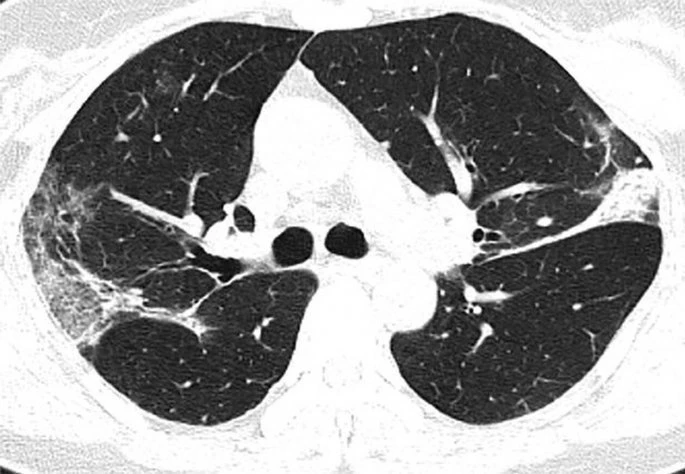

Η πανδημία του κορωνοϊού covid-19 συνεχίζει να καλπάζει σε όλο τον πλανήτη, με τους γιατρούς να παρακολουθούν την έξαρσή του. Περισσότεροι από 4.000 άνθρωποι έχουν χάσει τις ζωές τους από τις επιπλοκές του ιού, ο οποίος προκαλεί σοβαρό πρόβλημα στους πνεύμονες των ασθενών. Στην δημοσιότητα δόθηκαν από την Ραδιολογική Κοινότητα της Βορείου Αμερικής ακτινογραφία πνευμόνων ασθενών, οι οποίοι είχαν προσβληθεί από τον κορωνοϊό, οι οποίες προκαλούν ανατριχίλα.

Οι ασθενείς που έχουν νοσήσει μέχρι στιγμής έχουν περιγράψει την εμπειρία τους ως μια «τρομακτική προσπάθεια για να αναπνεύσουν». Στις ακτινογραφίες διακρίνονται κάποια άσπρα σημάδια, χαμηλά στους πνεύμονες. Περιγράφονται ως υγρό στις κυψέλες του πνεύμονα. Να σημειώσουμε πως οι ακτινογραφίες αυτές που δόθηκαν στην δημοσιότητα είναι από ασθενείς από την Κίνα που νόσησαν με επιπλοκές, οπότε δεν έχουν καμία σχέση με το αν νοσήσει κάποιος ο οποίος δεν αντιμετωπίζει προβλήματα υγείας.